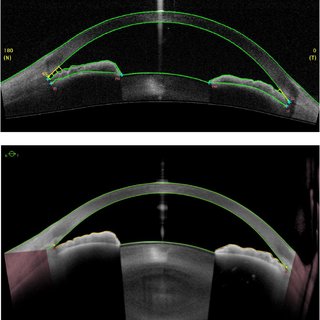

UBM vs OCT

UBM은

홍채에 가리는 홍채의 뒷부분까지 관찰이 가능하지만,

누운 자세에서 촬영해야하고,

눈에 직접 Probe가 접촉한 상태에서 측정을 해야합니다.

초음파가 공기를 통과하여 측정할 수가 없기 때문에, 환자가 누운 상태에서 눈에 깔대기를 씌우고 그사이에 물을 채운상태에서 Probe를 각막이나 공막에 대고 측정을하게됩니다. 즉, 직접 눈과 접촉한다는 점이 단점입니다.

검사자의 숙련도와 매우 밀접한관계가 있다는 것 역시 단점입니다.

OCT 안구 광학 단층촬영은 망막뿐아니라 전안부 촬영에도 사용되게되는데,

이를 Anterior segment OCT (AS-OCT), 전안부 OCT 라고 합니다.

최근나오는 AS-OCT는 각막의 영상뿐아니라 수정체 후면까지 찍을수 있는 해상도를 지닙니다.

이는 앉은 상태에서촬영하고,

눈에 직접 접촉하지 않고 측정가능하며,

UBM 보다 더 선명한 이미지를 보여줍니다.

다만 홍채뒷부분은 홍채에 가려서 측정이 불가능한 것이 단점입니다.